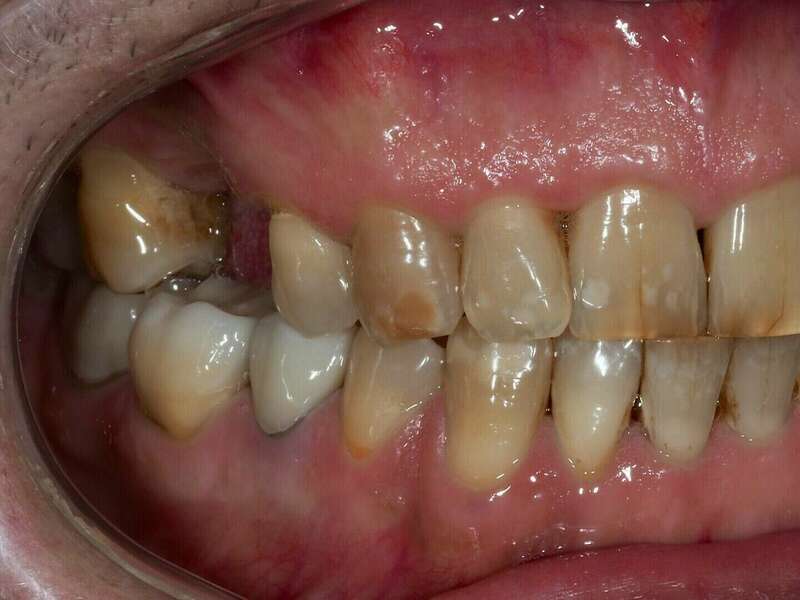

Patient venu en consultation pour une réhabilitation complète esthétique et fonctionnelle, les gênes majeurs étant les usures , les dents manquantes et la teinte de ses dent.

Avant